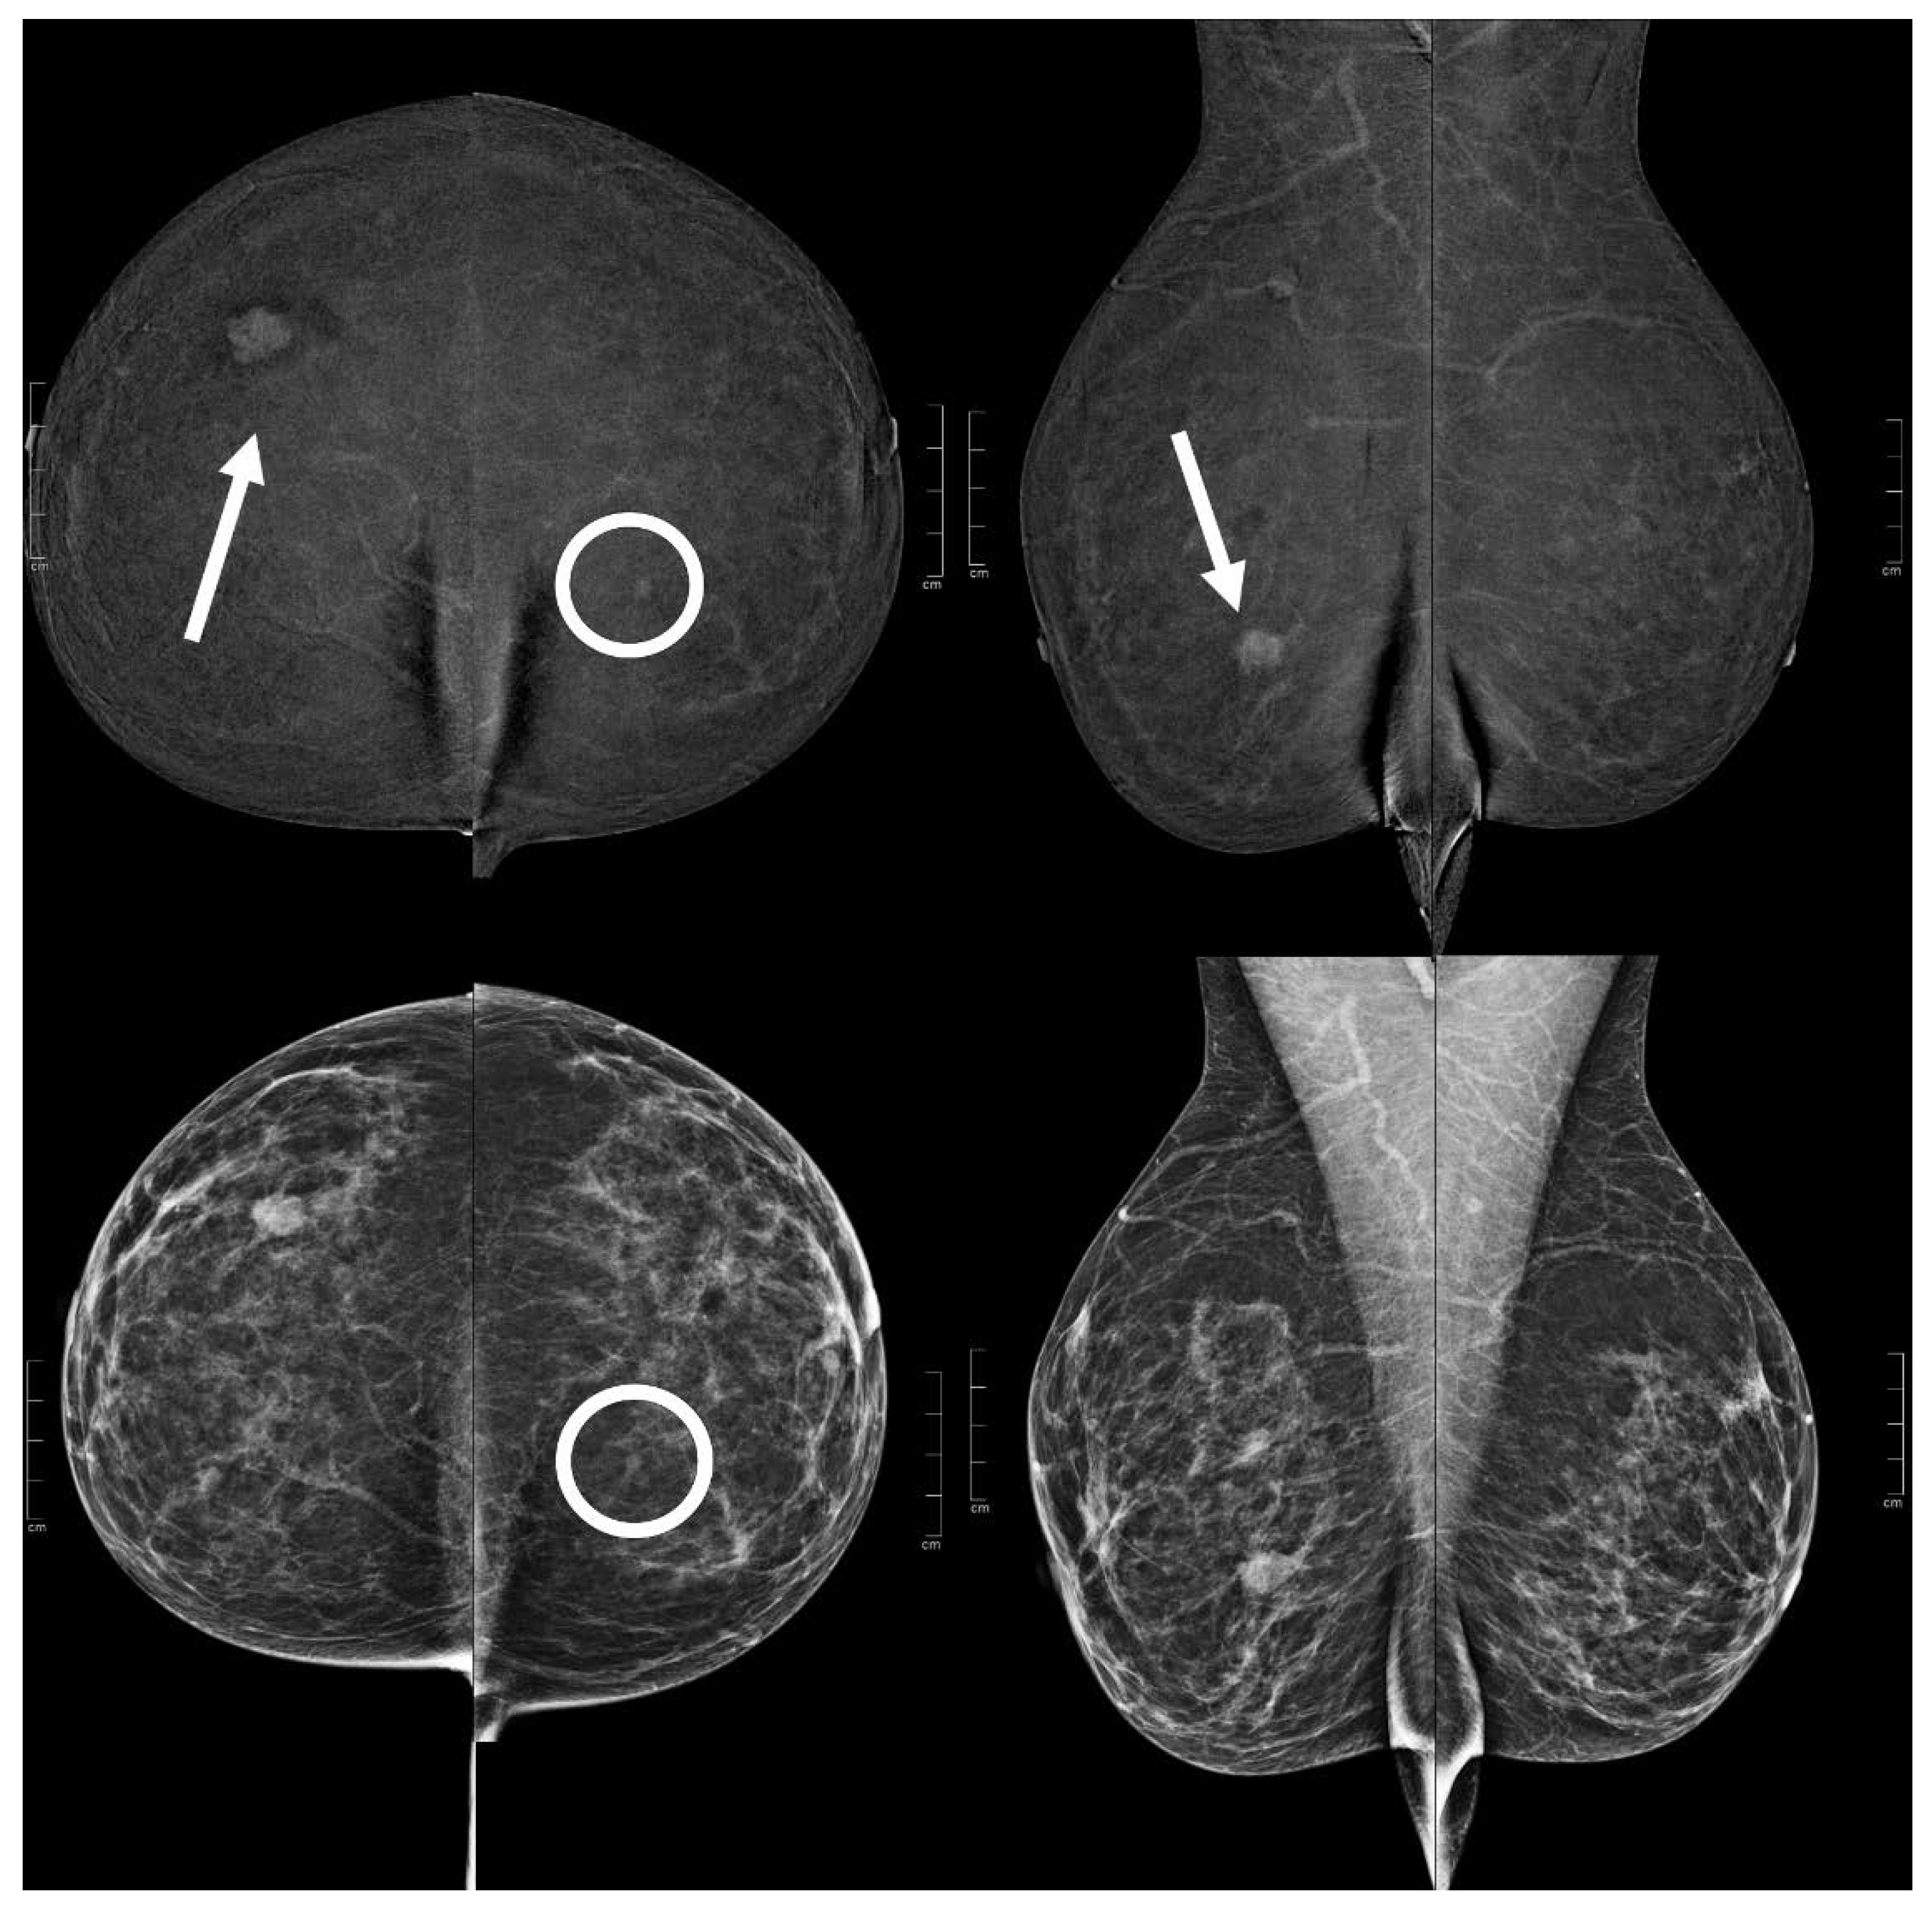

Figure 5.

A 51 year old patient. Contrast-enhanced digital mammography performed as preoperative staging for a B5 lesion in the right breast (arrows). In the early RC in the left breast, there was an enhancing asymmetry in the inner quadrants with moderate conspicuity only visible in CC (circle), corresponding to an opacity in low-energy images. This opacity subsequently underwent VABB (tomosynthesis-guided vacuum assisted breast biopsy), which confirmed an invasive carcinoma.